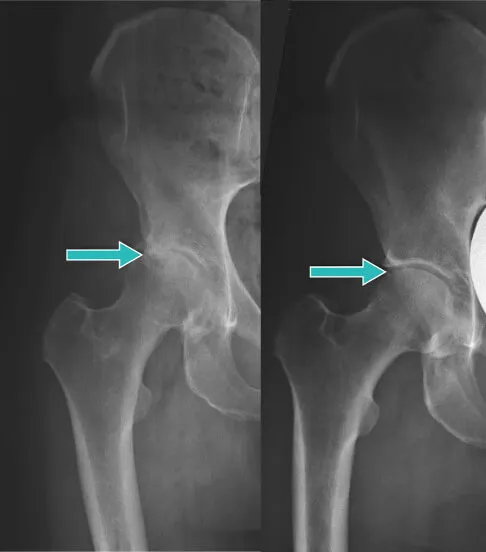

Guarda questo test effettuato su due pazienti.

Leonardo ha fatto usare a una donna una pomata da farmacia per un mese e un’altra donna ha usato lo spray Hondro Sol con Arnica montana e Boswellia Serrata.

Una donna che è stata curata con un unguento da farmacia non si è liberata del dolore:

Tuttavia, la donna che ha usato lo spray Hondro Sol…

… ha completamente curato la sua artrite

“Questo spray Hondro Sol è rivoluzionario. Facile da usare. E hai i risultati del trattamento più rapidi senza interventi chirurgici e unguenti costosi. Non ci sono nemmeno effetti collaterali. Altamente raccomandato.”